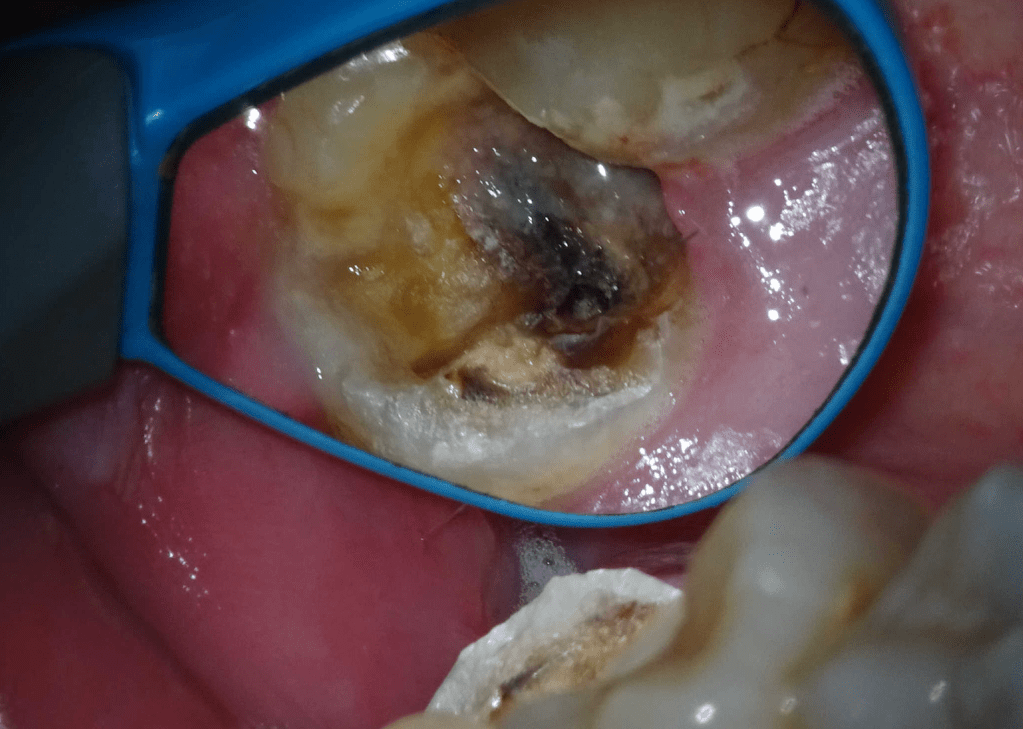

Pulpotomía biodentine + reco preendio